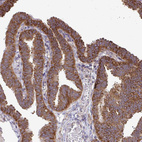

Immunohistochemical staining of human fallopian tube, liver, placenta and testis using Anti-FMR1 antibody HPA050118 (A) shows similar protein distribution across tissues to independent antibody HPA056084 (B).